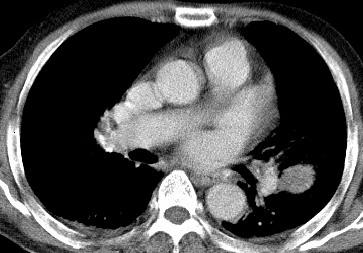

以下是引用光影相伴在2008-4-20 14:39:00的发言:[br]支持:1)左侧中央型肺癌伴左肺上叶阻塞性肺炎。、[br] 2)双侧少量胸腔积液。

以下是引用xianxianzhongyi在2008-4-20 14:44:00的发言:[br]本人愚见:次病例短短两月的时间,呈现如此大面积实变,病变增长过于迅速,此其一。其二,病变在动脉早期既有明显强化。其三,左上叶后段及下叶背段多叶受累。其四,肺门及纵隔内未见明显肿大的淋巴结。估计层面较厚段支气管显示不清。 诊断:炎性实变可能性大。